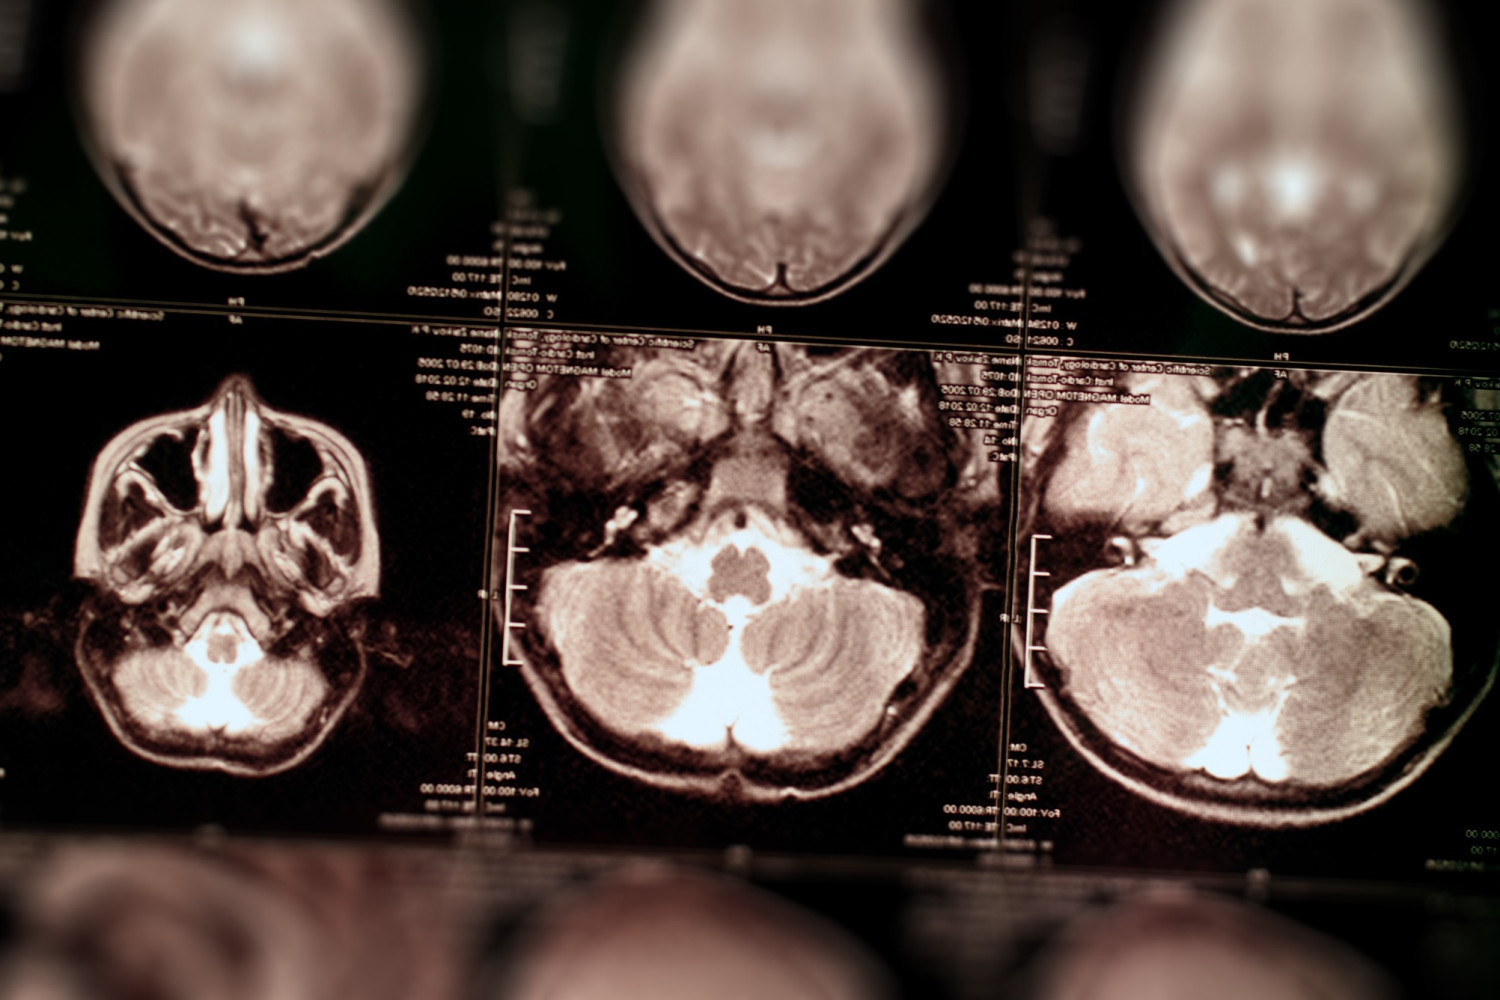

Ванг участвовал в разработке препарата simufilam, который представляли общественности как инновационное лекарственное средство от болезни Альцгеймера, а также диагностического теста для определения нейродегенеративного заболевания. Ученый подделывал данные исследований, за которые с 2017 года по 2021 год NIH выделили ему около 16 млн долл.

Simufilam принадлежит компании Cassava Sciences, на которую работает Ванг. Препарат проходит III фазу клинических испытаний. Утверждается, что NIH выступили главным спонсором проведения исследований лекарства.